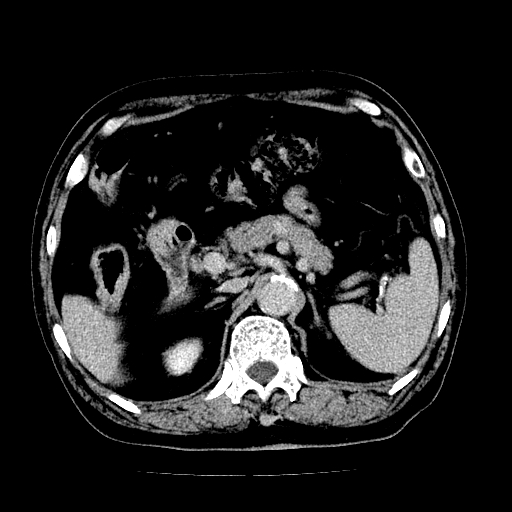

男,71岁,皮肤黄染四天。

肝内外胆管及胆总管上段扩张,考虑为梗阻所致,建议mrcp检查。

胰腺上端胆总管内见软组织影,强化不明显,结合临床,还是考虑低位梗阻性黄疸,胆总管癌可能性大